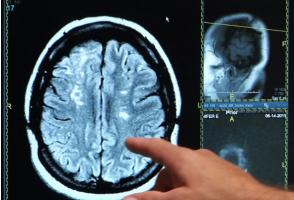

La pratique régulière d’une activité physique et un sommeil de qualité peuvent tenir la démence à distance, conclut cette méta-analyse menée à de l’Université York (Canada) : l’analyse des données de millions d’adultes d’âge moyen et de personnes âgées confirme, dans la revue PLoS ONE, l’importance de ces 2 facteurs de mode de vie pour un vieillissement cognitif en bonne santé.

On estime que 55 millions de personnes vivent avec une forme de démence dans le monde. Une prévalence qui ne va faire qu’augmenter, avec le vieillissement des populations. Les traitements actuels ayant une efficacité limitée, les efforts de santé publique devraient se concentrer également sur les facteurs de mode de vie pour réduire le risque de démence avant même l’apparition des symptômes. De nombreuses recherches ont déjà souligné le rôle d’un mode de vie sain pour préserver la santé cognitive, cette étude précise leur lien avec la démence.